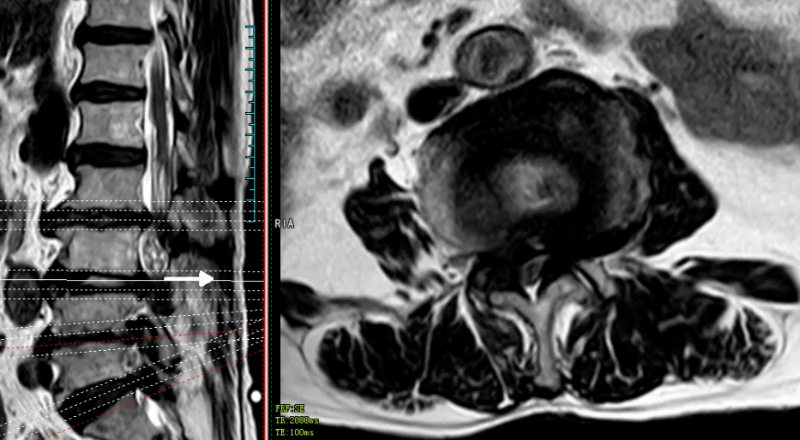

84岁高龄的田婆婆(化名)反复腰腿痛、双下肢麻木、间歇性跛行多年。近半月来病情不断加重,已严重影响生活。于今年的5月份,到我院脊柱外科就诊。经检查,诊断田婆婆腰椎椎管狭窄严重,压迫马尾神经导致马尾综合征,有明确手术指征,但田婆婆已84岁,合并有众多基础病,手术创伤大,风险高,而通过UBE技术进行减压同样可达到减压的目的,且手术创伤小,出血少。

术前MR可见腰3/4、腰4/5椎间盘突出,伴椎管狭窄严重、神经根受压、马尾神经冗余。